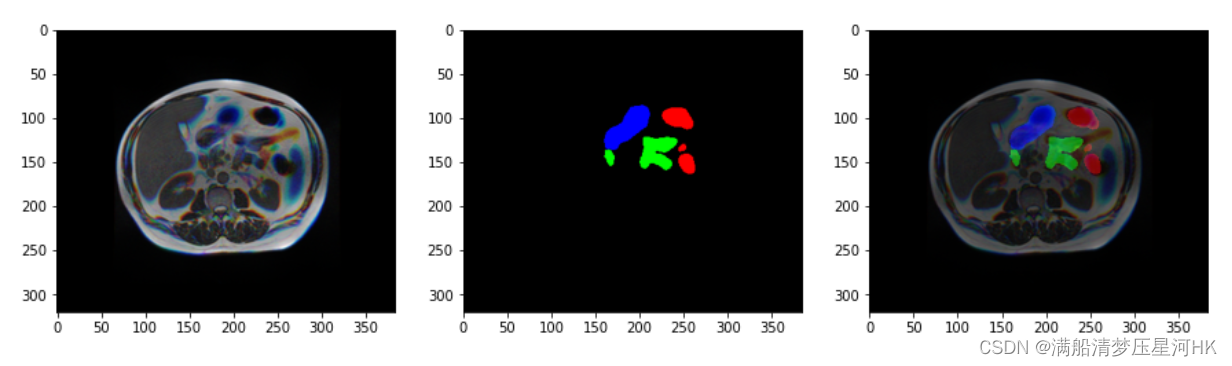

原先的数据是单通道的数据,为了让这种单通道的数据能在2D的网络上跑起来,baseline是将每个图片复制3份,然后直接concat拼接,送入网络进行训练的。

2.5D的思路:对于slice3这张训练图片而言,我不再是把slice3复制3份再concat送入网络了,而是将slice1、slice3、slice5这三种图片concat起来,再送入网络中训练,mask还是实验slice3的mask。依次增加模型的深度信息/空间上的信息。

2.5D改造后的图片和mask: